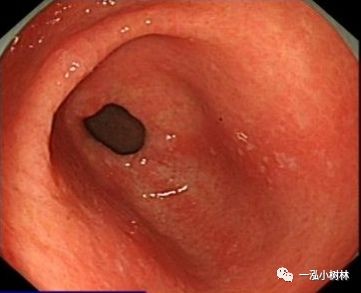

例2

女性,60岁,慢性萎缩性胃炎伴肠上皮化生,Hp+